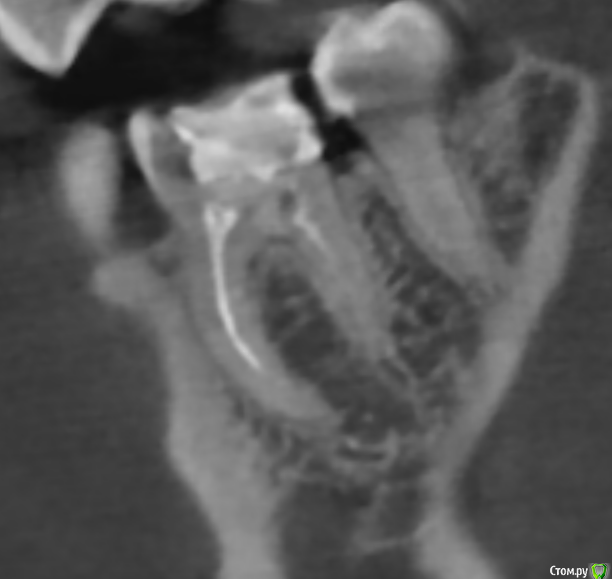

Антон999 Опубликовано 7 января, 2020 Поделиться Опубликовано 7 января, 2020 Здравствуете, имеется депульпированный нижний шестой зуб, пролеченный и с запломбированными каналами, после оценки собственных тканей зуба (коих осталось примерно 40-50% на взгляд врача) было предложено протезирование культевой вкладкой с коронкой, выбор материала культевой вкладки состоит либо из диоксида циркония либо из кобольто-хромового сплава. Из соображений биосовместимости я склоняюсь к диоксиду циркония и хочу спросить у вас совета, оправданно ли ставить разборную вкладку из ДЦ на жевательный зуб? Не будет ли это решение плохим ввиду каких-то недостатков перед КХС в плане надежности и безопасности для зуба? В кобальто-хромовом сплаве меня смущает, что исходя из некоторых источников подобные неблагородные металлы влияют на физико-химические показатели ротовой жидкости при продолжительном использовании. Или я где-то ошибаюсь и современное протезирование предполагает, что конструкция будет герметична, то есть не только вкладка, что накрывается коронкой, но и металлический каркас «шейки» металлокерамики не будет контактировать с агрессивной средой ротовой полости даже спустя несколько лет? (пару снимков из кт зуба прилагаю) Ссылка на комментарий